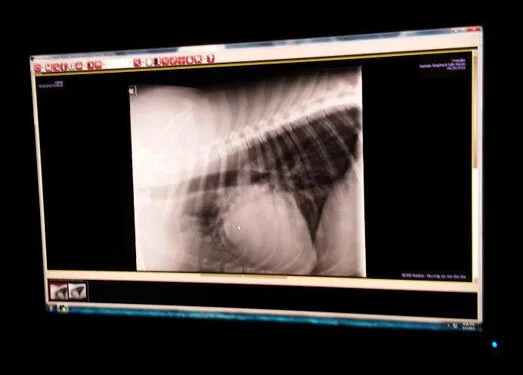

Wrangler spent most of today at the hospital again in isolation. More fluids & meds were administered and x-rays were taken. We found out that he is battling pneumonia so a nebulizer was used to more effectively deliver the meds into his lungs. He is resting in a foster home tonight but will need to go back to the hospital in the morning for another round of fluids & meds. His vet bills are climbing and we need your help!! If you can donate to Wrangler’s care, that will help us tremendously! Please spread the word to your friends and family. Even a small donation of $5 will help!! Thank you to those of you who have already donated to his care, we very much appreciate your generosity. Wrangler is not out of the woods yet so please keep him in your thoughts and prayers.